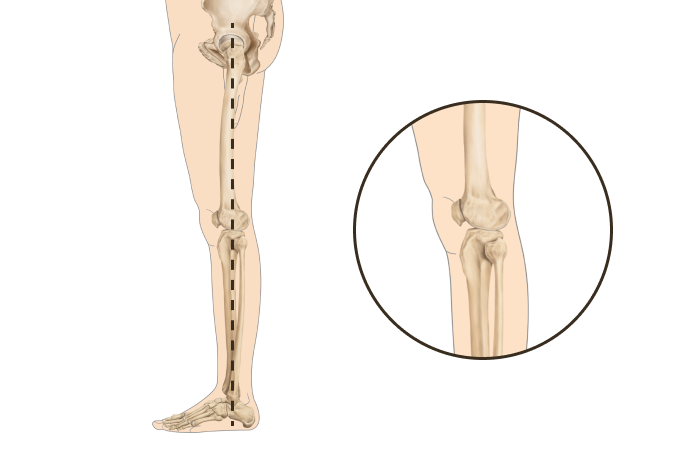

▲ O자 다리

▲ 정상 다리

휜다리의 대표적 유형 2가지

O다리

• 무릎이 외측으로 벌어지면서 다리 축이 변형됨

• 체중부하가 다리 안쪽(내측)에 집중되어 내측 관절의 압력증가로

무릎관절의 퇴행성 변화와 통증을 초래

• 허벅지 안쪽 근육이나 엉덩이 근육이 약화되면 무릎 안정성이 떨어져 내반슬이 악화

휜다리는 단순히 무릎 사이 간격이 벌어진 것이 아닙니다.

무릎 위의 대퇴골과 아래의 정강이뼈가 회전하면서 무릎까지 뒤로 빠지기 때문에 다리사이 간격이 넓어지는 겁니다.